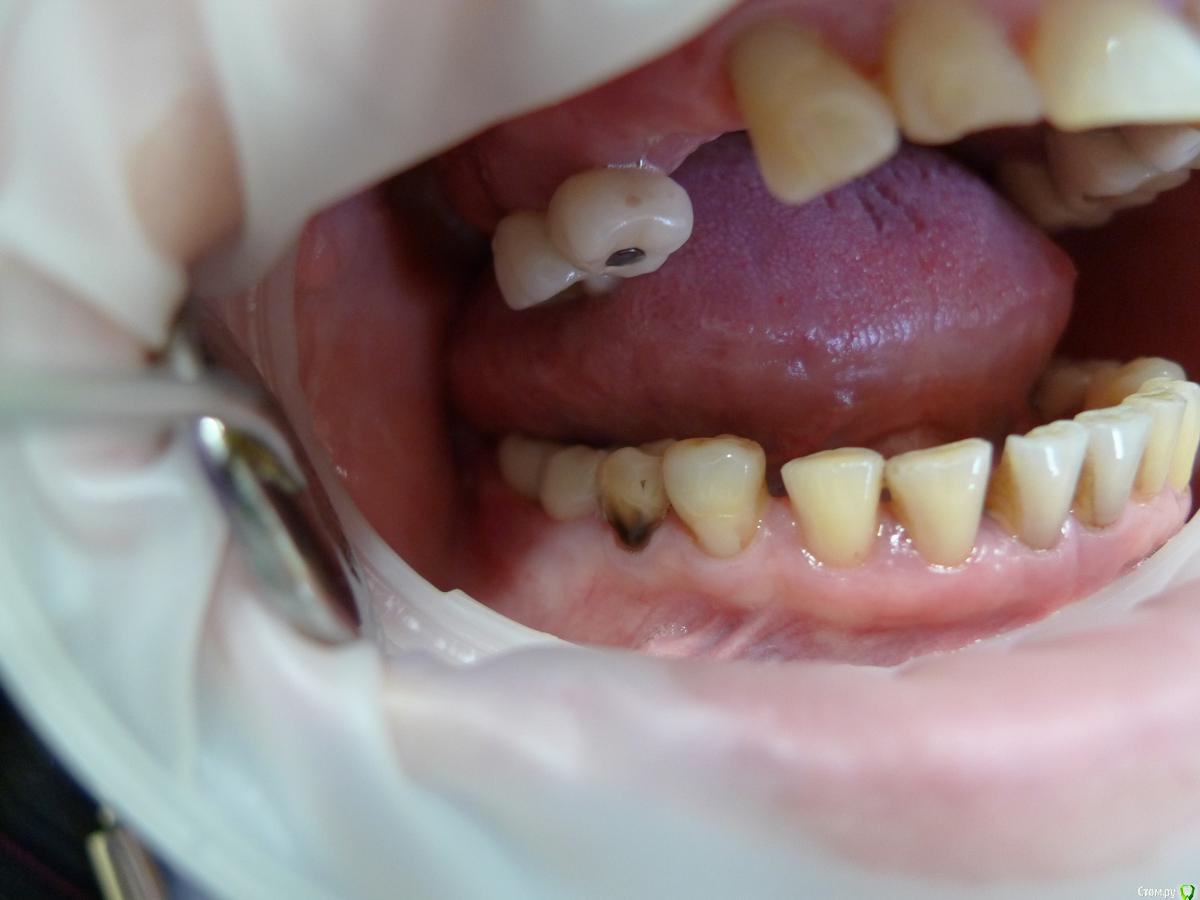

alekszander Опубликовано 25 февраля, 2016 Поделиться Опубликовано 25 февраля, 2016 Пациентка 45-го г.р. Из анамнеза: имплантация была проведена более 10 лет назад. Имплантаты на тот момент очень популярные и ставил человек минимум КМН на тот момент, а может уже и выше. Со слов пациентки - имплантат 1.4 закачался и выпал несколько недель назад. Пациентка никаких болей не отмечает. Общее соматическое состояние - удовлетворительное. Сахар на границе +- от нижней нормы, но диабет не ставят. Были проблемы с щитовидной железой (что точно не помнит), насколько понял из анамнеза - тиреоидит вроде. Когда-то была язва (более 20 лет назад) Не курит, не пьет. В целом жизнерадостная женщина и даже не выглядит на свой возраст. Вопрос как так? В 3-м квадранте все гуд, в остальных такая опа. Со стороны полости рта - имплантаты покрыты слизистой до уровня МК коронок. На момент обращения при пальпации обильное гнойное отделяемое, но болевых ощущений нет! Назначил АБ+НПВС+АГ+ХГ местно. Сегодня пришла: гной сохранен только в области 2.3,2.4,2.5,2.6 но уже скудное отделяемое. Пальпация по прежнему безболезненная. Слизистая без грануляций, розового цвета (поверхностно) Из вариантов - по хорошему: на выход имплантаты 1,2,4 квадранты+зубы 1.3,2.3. Временные съемные. Общий анализ крови и совместное наблюдение с эндокринологом. По поводу повторной имплантации чет- сомневаюсь, но нужны будут анализы. По плохому (умаляет пациентка,т.к возраст уже такой, что повторно не готова а съемное не хочется) сохранить имплантаты и диспансерное наблюдение. Правда тут у меня вопрос в голове, а что делать с 1.4,1.3,2.3 в плане протезирования?.... Коллеги прошу помощи, ситуация не однозначная. Прилагаю ОПТГ через год после протезирования и 2 недельный снимок. Ссылка на комментарий

alekszander Опубликовано 26 февраля, 2016 Автор Поделиться Опубликовано 26 февраля, 2016 Прилагаю фото в полости рта (прошу прощения фото на мыльницу Leica) - ретракторов и зеркал пока нет. Ссылка на комментарий